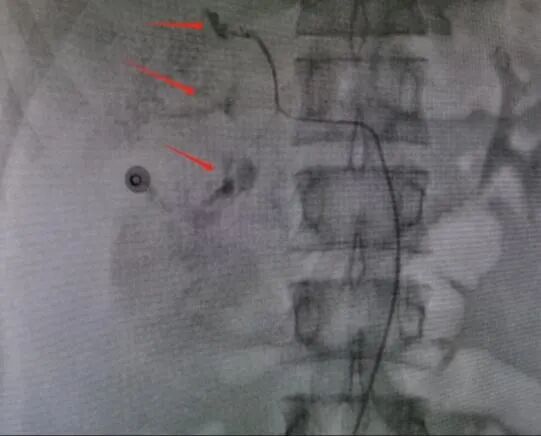

术后DSA造影图

救治方案明确后,患者立即被推入了手术室,在邓文军总监的指挥下,一场惊心动魄、紧张有序的手术开始了。各专科主任严阵以待,在院待命,随时做好开腹手术准备。介入手术由影像中心副主任兼介入组组长吴继雄主任医师亲自主刀,手术过程顺利,术中造影找到右肾脏有几处明显的活动性出血点,肝脏也有两处活动性出血点,给予及时栓塞止血后,再次造影无明显出血。整个手术仅约一个小时,刀口仅针眼大小,术中病人情况稳定,失血量不到10ml,患者成功脱离生命危险,术后被送入ICU密切观察诊治。病情平稳后转入普通病房,经过后续治疗目前该患者已经平安出院,出院时状态良好已经能自行走路。